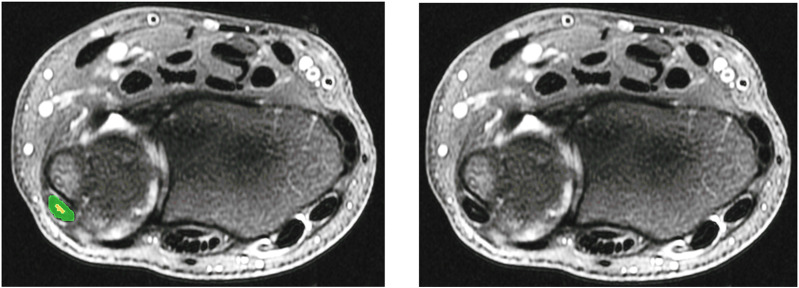

Results: The mean ECU tendon segmentation Dice score ranged from 0.61 to 0.64 (± 0.27 to 0.31). Tendinosis detection yielded a Dice score of 0.38 for both the threshold method (±0.19) and the CNN (±0.22). A Dice score > 0.50 indicated successful detection, with our methods achieving a detection rate of 72-76%.

Conclusion: The developed CNN effectively detected and segmented the ECU tendon in 2D MRI series. Tendinosis was detected with comparable accuracy using both signal intensity thresholding and the trained CNN method.